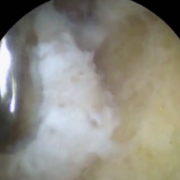

Then I turn my attention to the ossicle itself. I use a probe and then I shave it free from the softer tissues encasing it, and then I use a grasper to take it out. You can see the ossicle sandwiched between the ends of the grasper. It looks quite big but the camera magnifies it, and also there is soft tissue surrounding it.